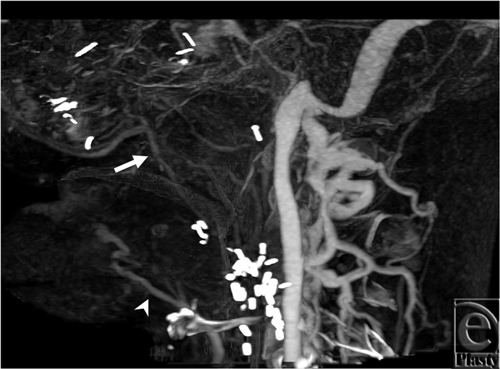

Subject 3

The cine images (see Movie 3 [Click Here for Video]) demonstrate delayed filling of the left facial artery territory, suggesting some retrograde flow, particularly in the setting of a prominent right facial artery. The arterial phase static image with best enhancement shows a fully opacified facial and lingual artery, without signs of retrograde flow (Fig 2). The right superficial temporal artery was hard to identify in the cine loop because of larger vessels obscuring it, whereas the static image illustrated the superficial temporal artery as the terminal branch of the external carotid artery (Fig 2).

![]() |

| Figure 2. Best arterial phase from subject 3. Facial arteries (arrows) are well opacified and look normal on both sides. The right superficial temporal artery (arrowhead) is also well depicted. |